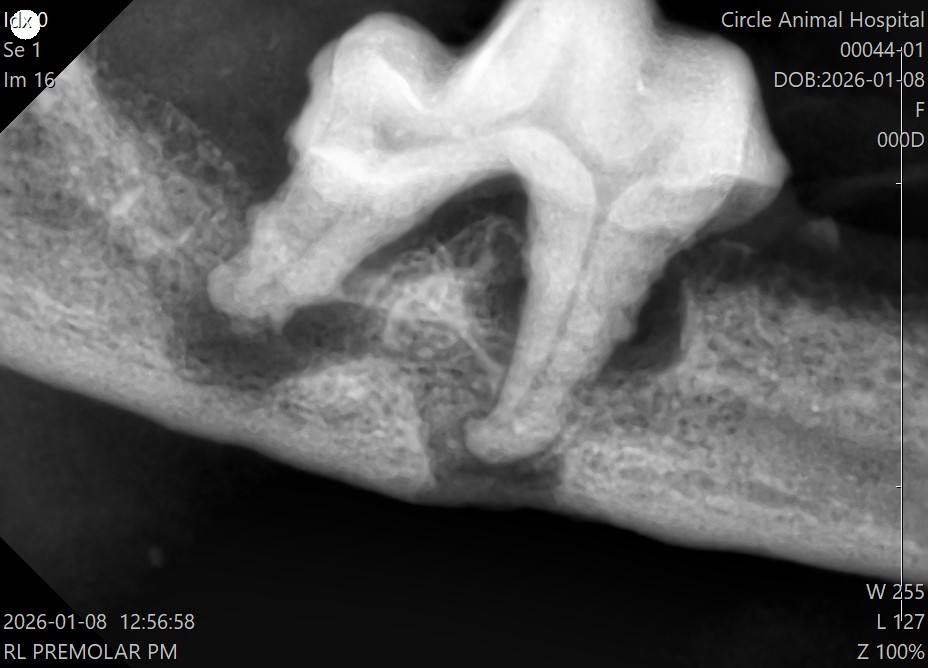

その後に、歯科レントゲンを撮影し、肉眼では見えない歯の根っこの部分を評価します。

レントゲンでは、

・歯を支える骨(歯槽骨)が大きく溶けている

・歯根の周囲に炎症が広がっている

状態が確認されました。

見た目以上に、歯周病は深く進行していました。

特に右下顎の歯根部では下顎骨がかなり溶けてしまっており、骨折する可能性がある状態でした。